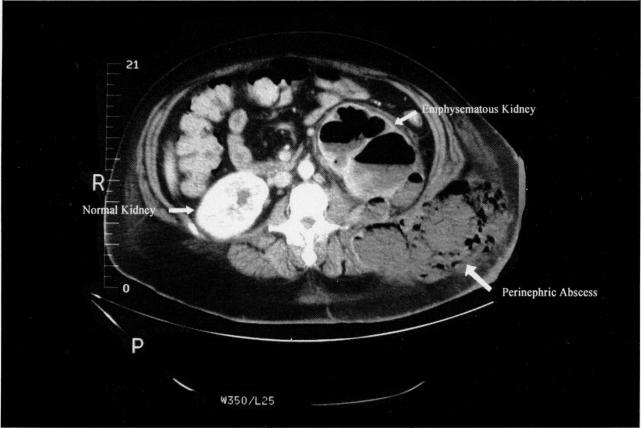

Emphysematous pyonephrosis is a rare, rapidly progressive infection characterized by the presence of exudative material and fermentative gases within a dilated renal collecting system. This unusual clinical entity is noted almost exclusively in diabetic patients, often in conjunction with chronic urinary tract infection and obstruction. In most instances, E. coli is the etiologic agent; however other enterobacteriaceae may be isolated. High fever, leukocytosis, renal parenchymal necrosis and the accumulation of gases in the kidney and perinephric tissues are the hallmark of this condition. Surgical resection of the involved tissue and systemic antibiotic administration are among the primary mainstays of therapy. We present a unique case of a pregnant patient with fulminant emphysematous pyonephrosis and the successful treatment rendered.